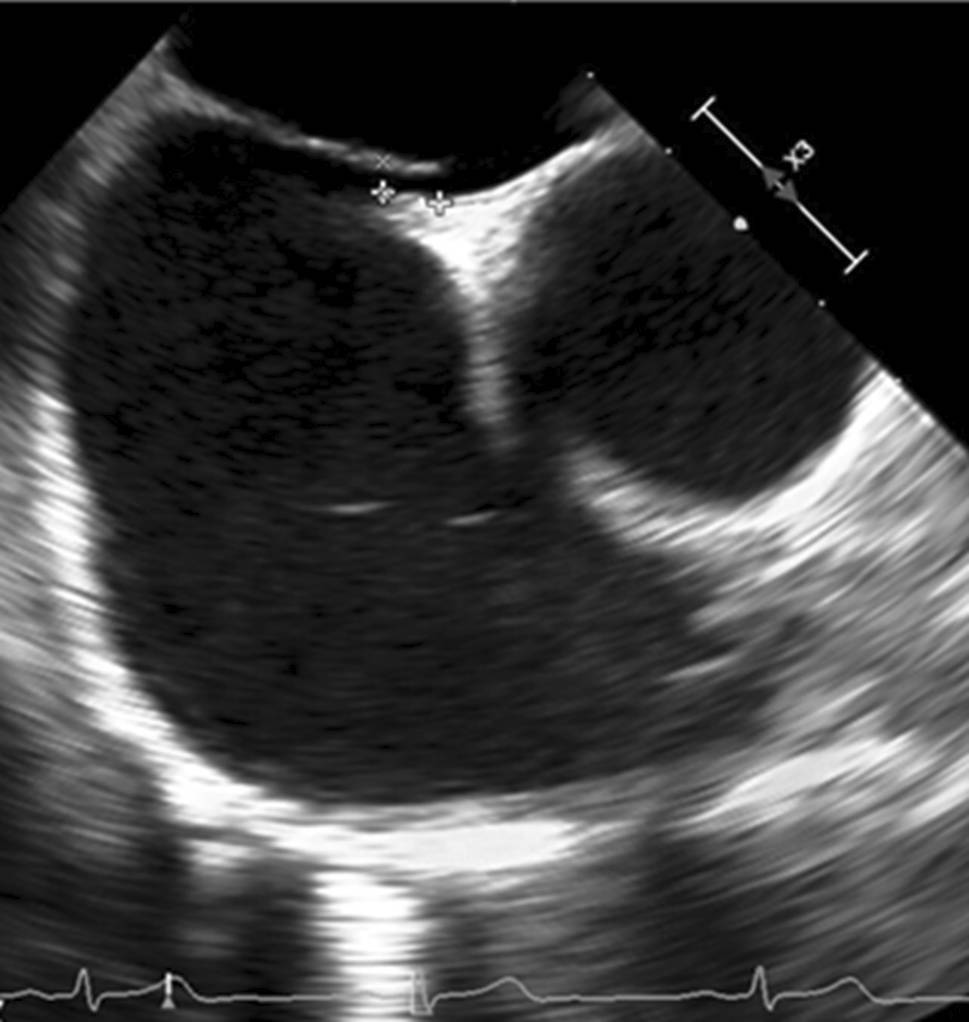

The results of TEE imaging were also recorded to further assess the PFO characteristics. Anatomical PFO characteristics were measured with standard TEE imaging (Epiq, Philips, Best, the Netherlands, and Vivid E95, GE Healthcare, Horten, Norway). The PFO size was measured with two-dimensional TEE before PFO intervention as an “unstretched diameter” in 114 patients (Fig. 2) or with three-dimensional TEE during PFO intervention, after placement of a guidewire through the PFO, resulting in a maximal “stretched diameter” in 109 patients (Fig. 3). Atrial septal excursion was measured on an image with the best cross section of the atrial septum between 30 to 60 degrees (Fig. 2).

Fig. 3

TEE image of a stretched PFO